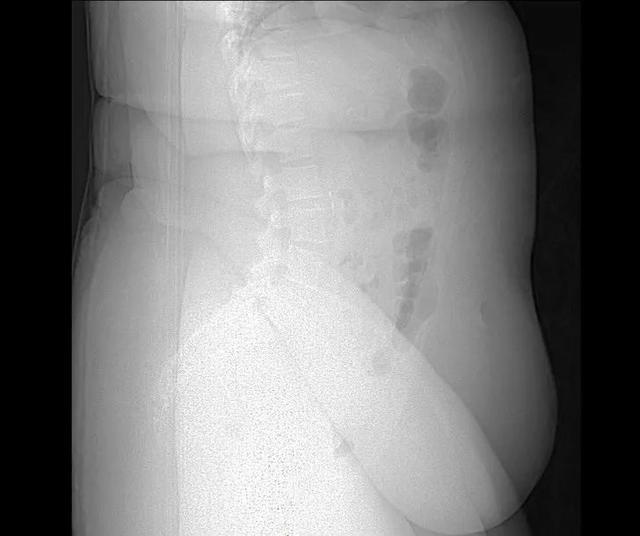

胖子的X光照片,脂肪过多导致骨骼都很难看见